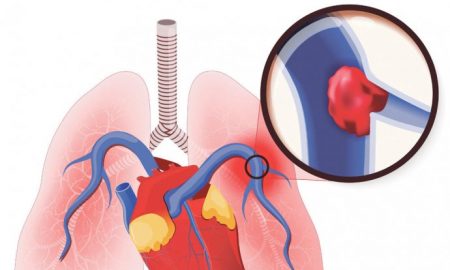

61.7KZdravljeOVO SU 2 ZNAKA DA IMATE TROMB U PLUĆIMA : Ljekari upozoravaju da ako ih osjetite, morate odmah u bolnicu !

Jedan od savjeta ljekara kako spriječiti stvaranje krvnih ugrušaka je da pijete puno vode jer je dehidracija takođe faktor rizika.